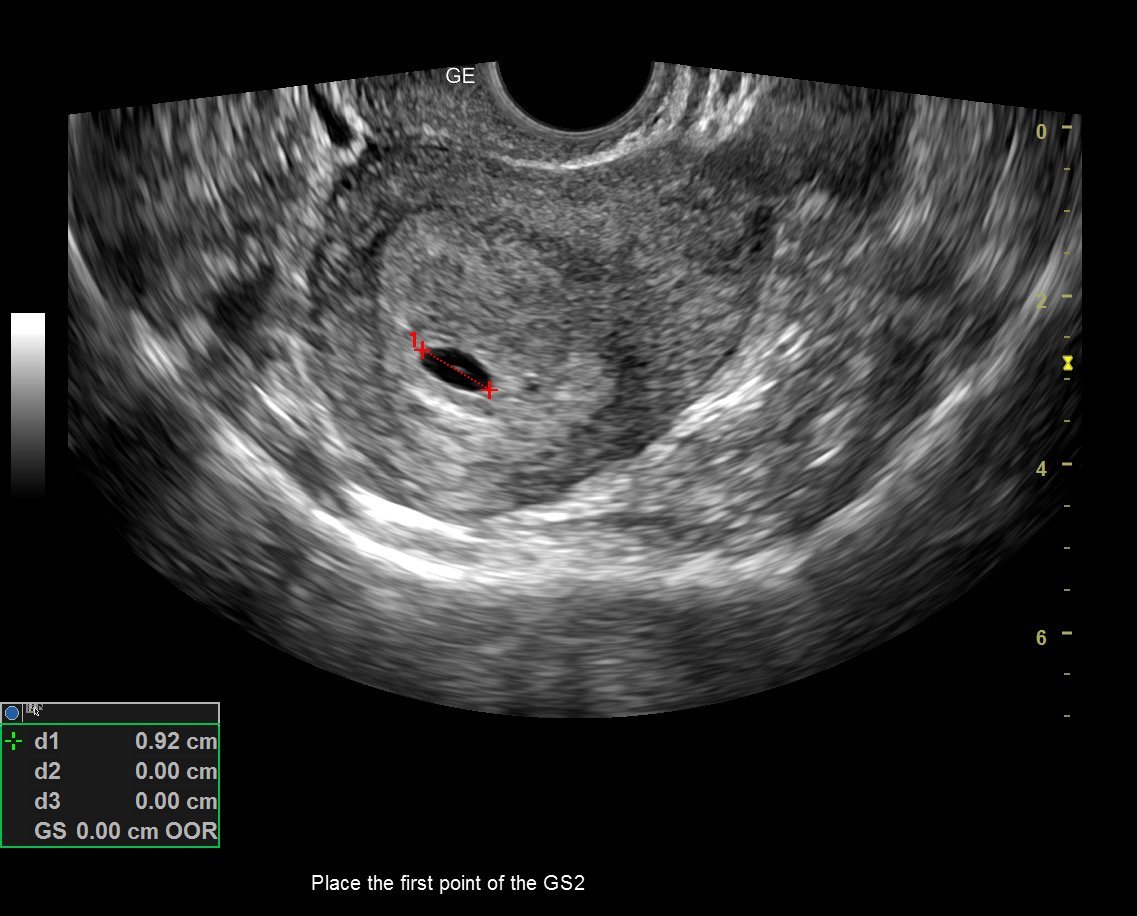

Здравейте тази снимка отговаря ли за 6 г седмица

Каза че съм в 6 седмица нищо повече ?

Да!